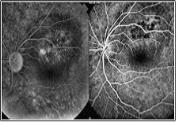

형광물질을 정맥주사 후 망막 혈관을 촬영하는 검사입니다. 망막 내 위치 및 종양의 크기를 보다 정확하게 알 수 있는 진단 방법입니다.

[ 형광안저촬영 ]